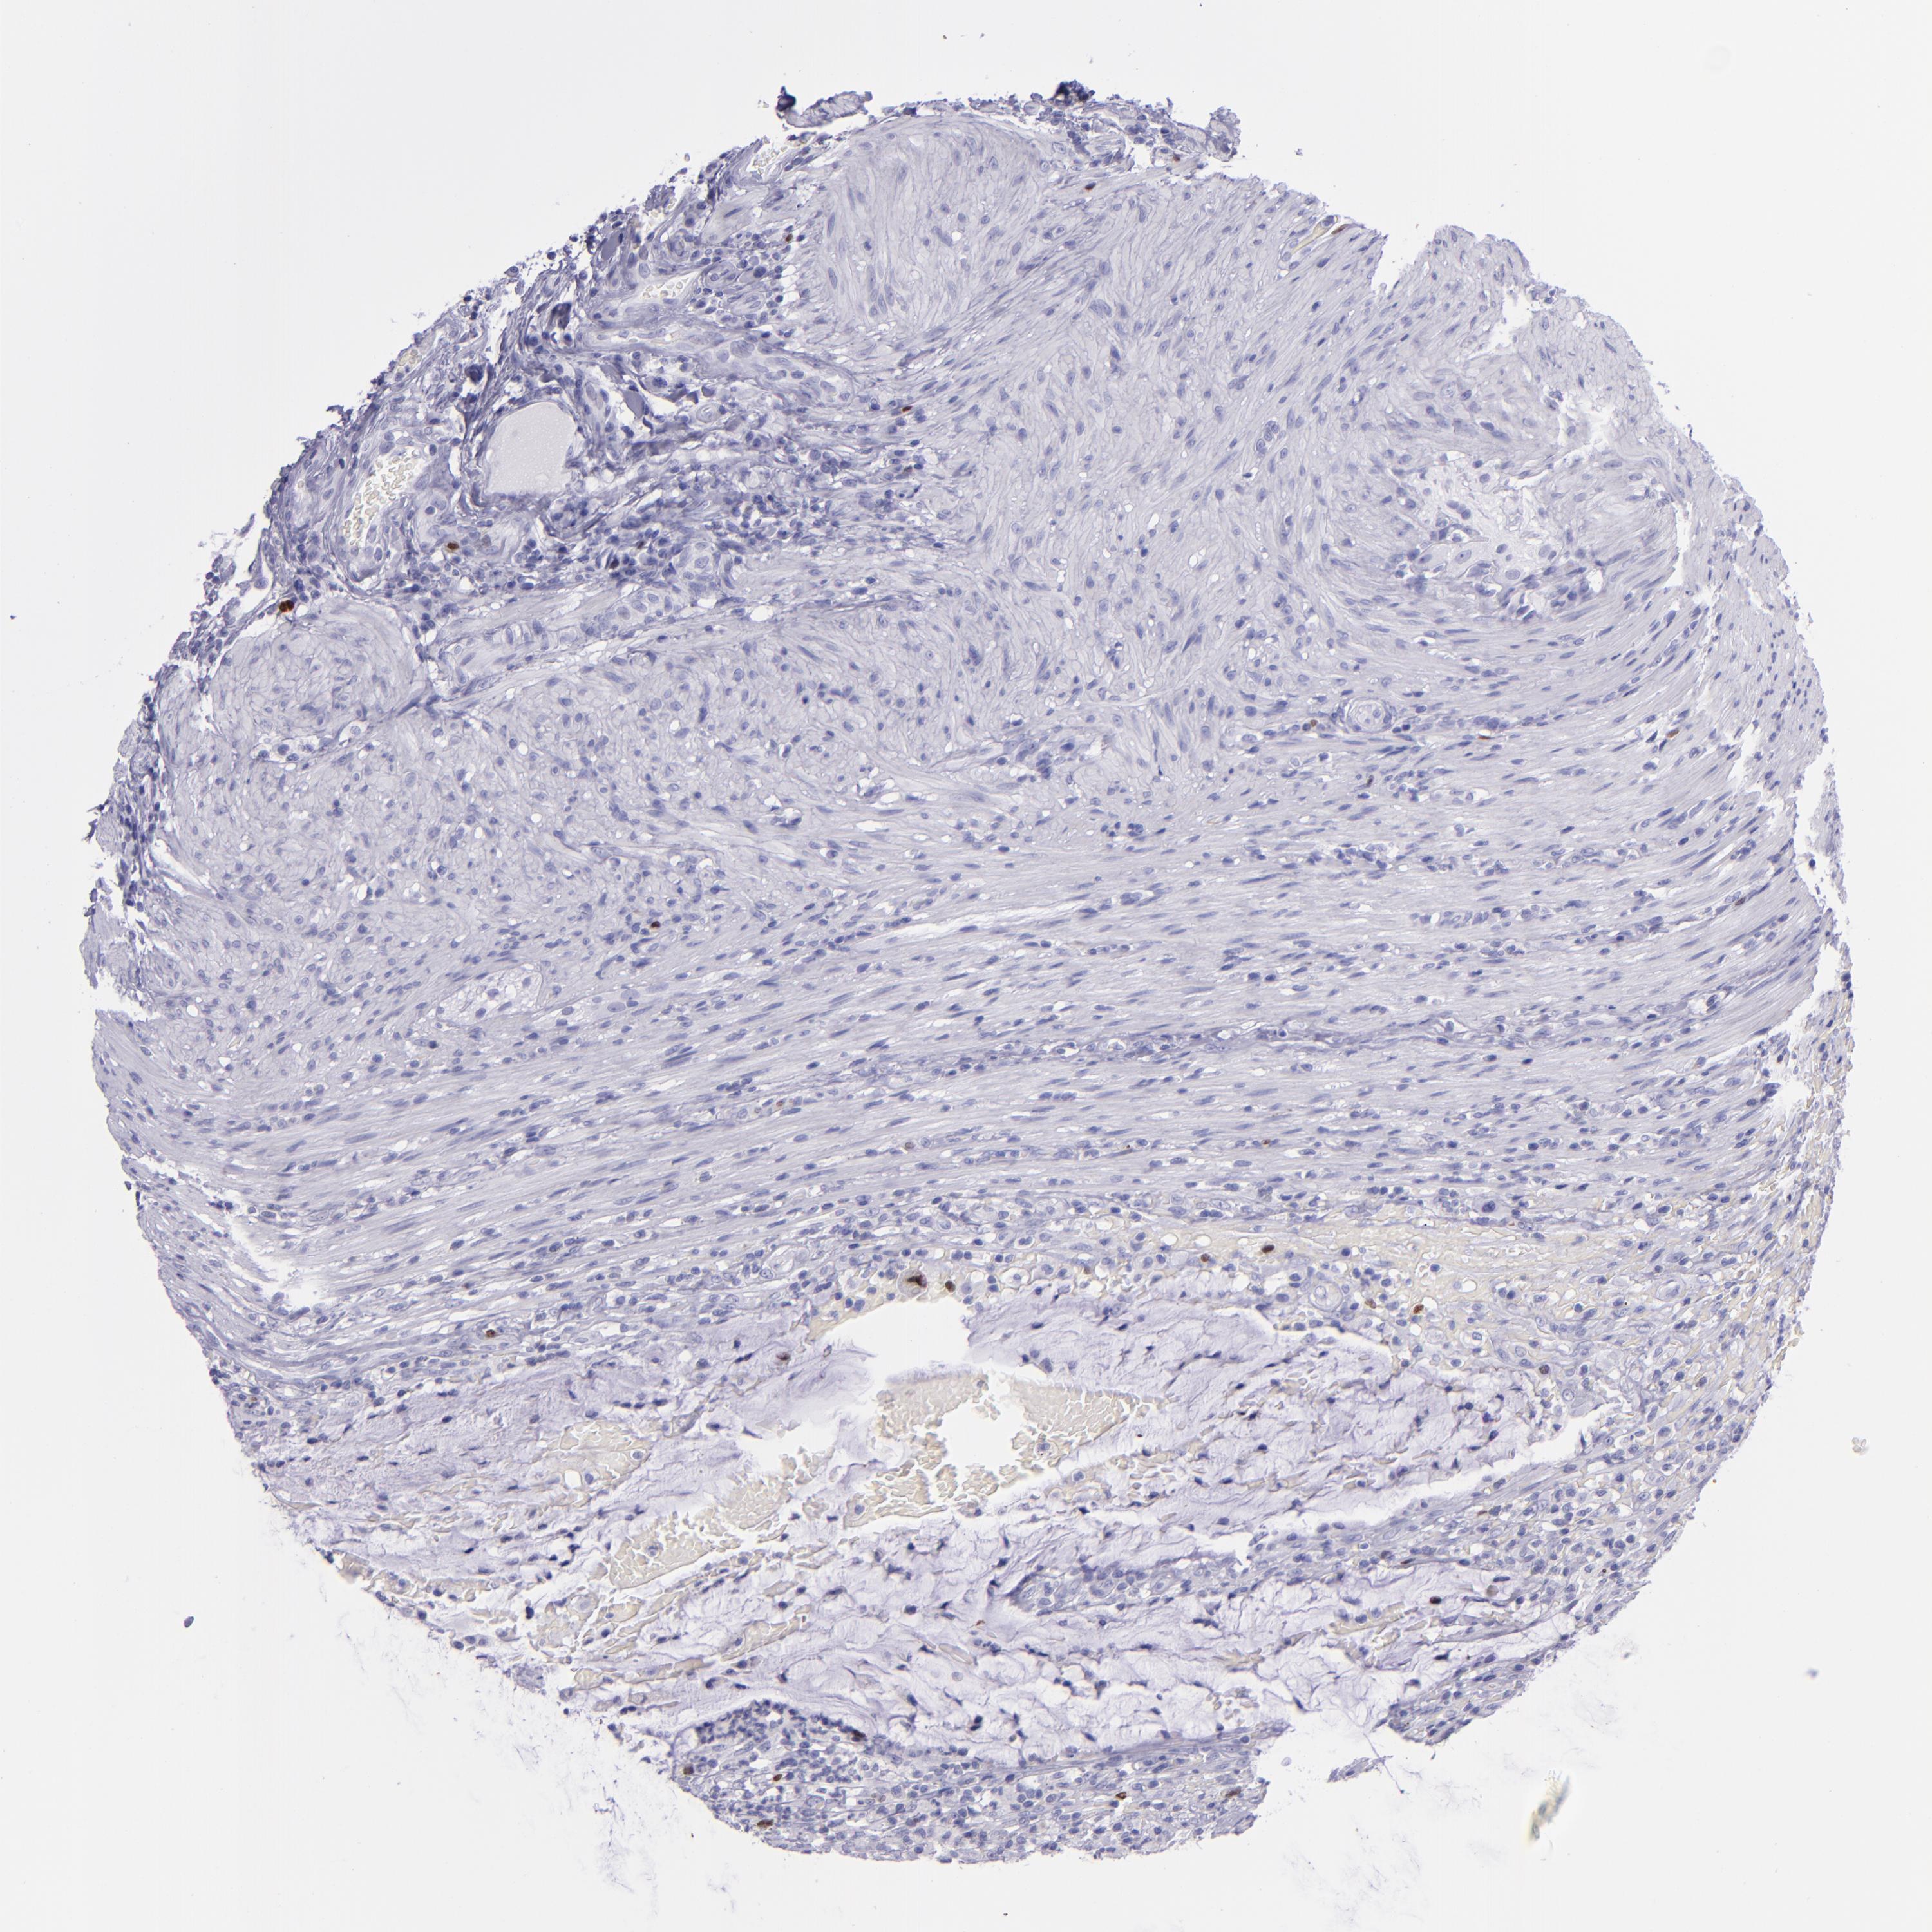

CANCER COLORECTAL CANCER Show tissue menu

ANTIBODIES

AND

VALIDATION